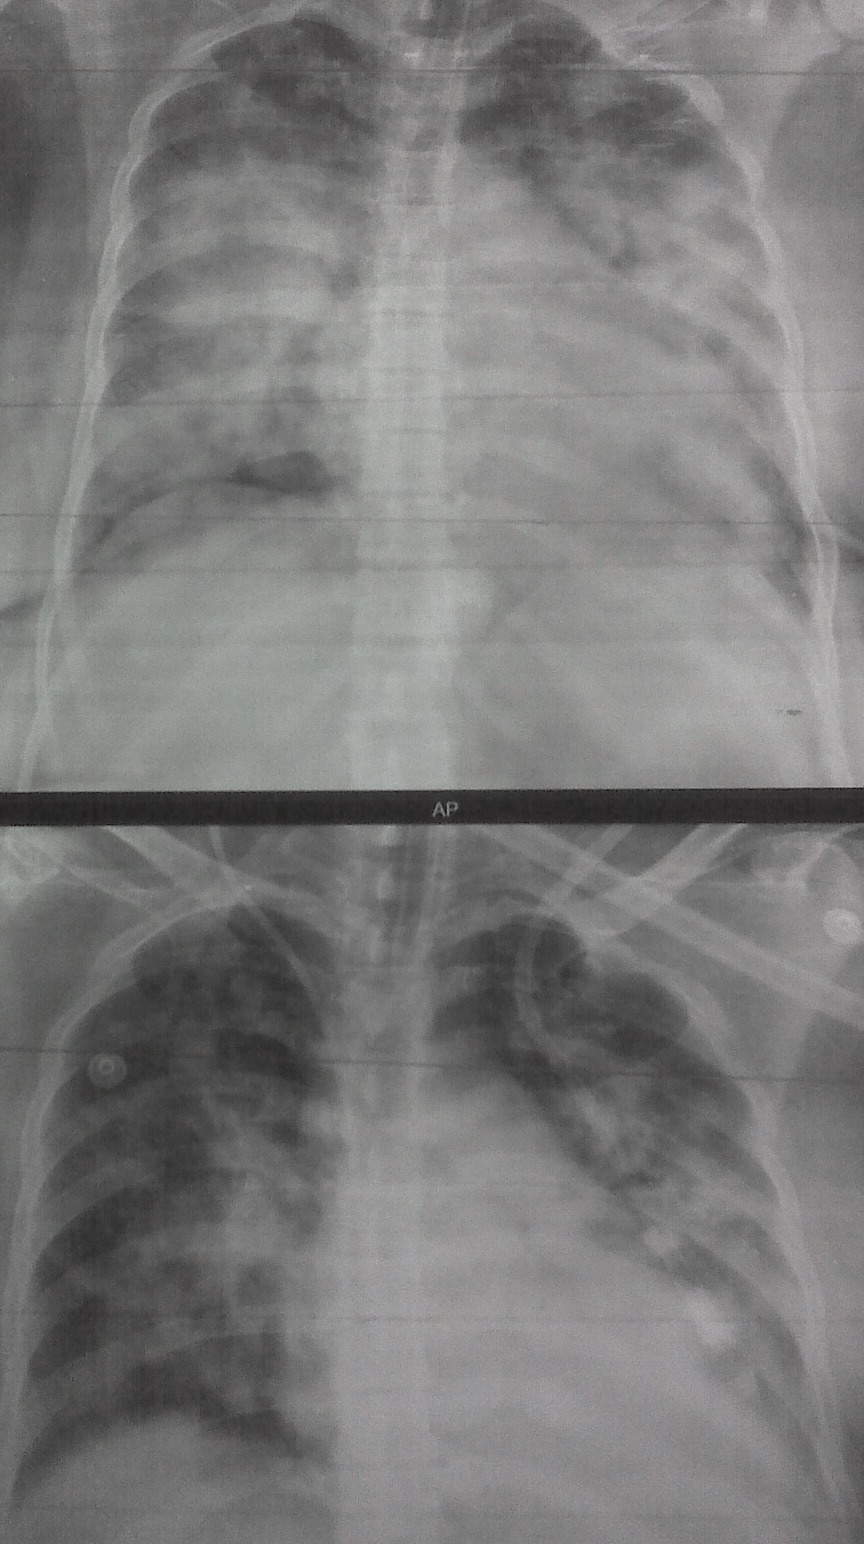

Pulmonary Edema CXR Sumer's Radiology Blog

Pulmonary Edema CXR Sumer's Radiology Blog Can Pulmonary Edema Be Seen On Xray Pulmonary edema is one of the most common entities encountered on routine chest imaging in both the inpatient and outpatient settings. Learn how to recognize the chest radiographic signs of hydrostatic and permeability pulmonary edema, and the factors that affect their appearance and resolution. Doctors may also order tests to confirm pulmonary edema or to rule out other conditions, including:. Can Pulmonary Edema Be Seen On Xray.